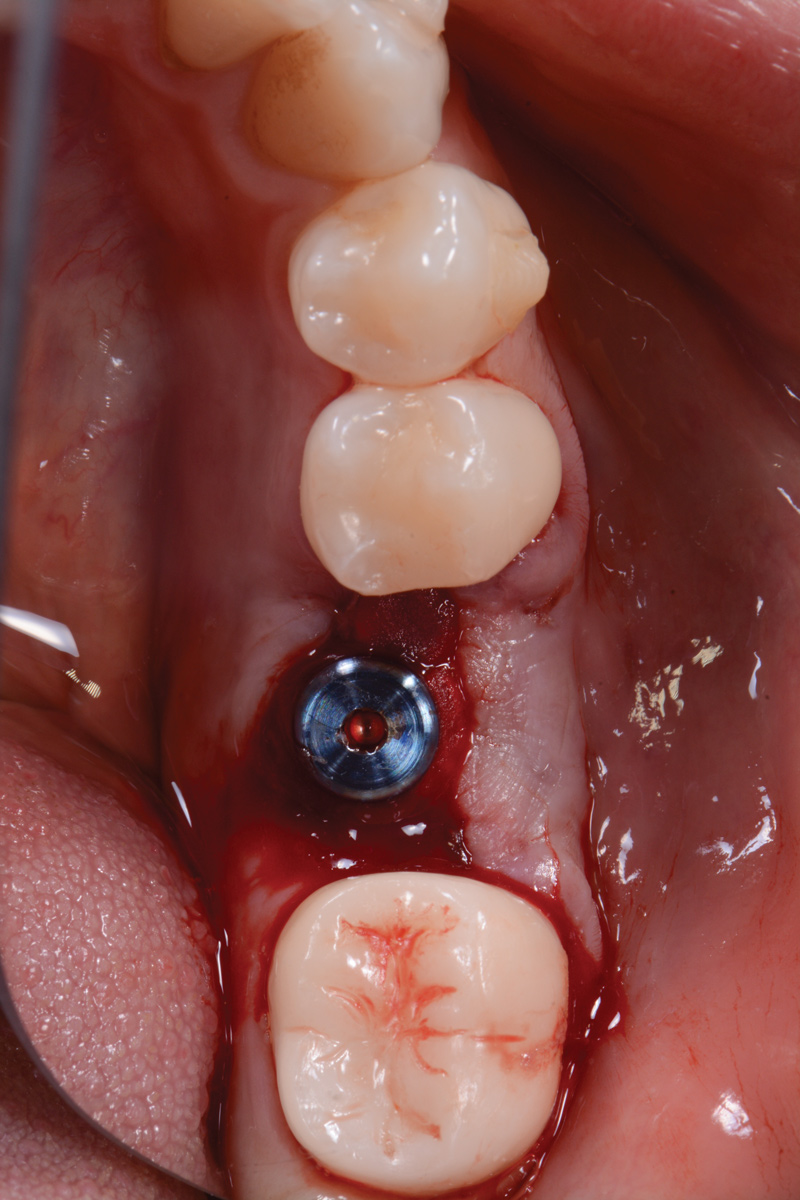

The following day, the patient presented for an emergency, reporting she began to bleed after she left the office and had continuous bleeding that day and night. Vital signs were normal (blood pressure was 115/65 mmHg, and pulse was 53 beats per minute). The first attempt to control the bleeding included having the patient bite on wet collagen wound dressing and alternate using wet- and dry-gauze compression for 30 minutes. After the removal of the collagen wound dressings, the bleeding restarted spontaneously. The sutures were then removed, and a collagen wound dressing was placed under the flap. Two single interrupted sutures were used, and a third suspended suture was placed around the healing abutment to obtain compression in the area. The patient was observed for 1 hour. During this time, wet-gauze compression was used on the area until the bleeding stopped. The patient was then dismissed and told to reapply gauze with pressure if bleeding recurred (Figure 1 through Figure 5).

Fig 2. One day postoperative.

Figure 2